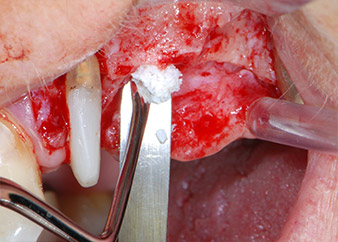

total loss of bone and attachment

Fig. 2 and 3: After raising flaps, one month after endodontic revision and initiation of full-mouth periodontal therapy, the buccal root of tooth 24 showed a total loss of bone and attachment.

One month later, on the day of surgery, pain and inflammation at tooth 24 were minimal, but mobility of Miller class 2 was still present. After opening the flaps and cleaning the periapical and peri radicular infected tissue, the extent of the bone defect became obvious (Figs. 2 and 3).

At the buccal root, all vestibular and distal bone was missing. Attachment was essentially restricted to the palatal root, underlining the preliminary poor prognosis. Tooth 27 also showed a reduced horizontal attachment and a minimal apical rarefaction (cf. Fig. 1) without clinical symptoms.

However, we maintained our initial plan to retain both teeth as temporary bridge abutments during the six-months osseointegration period of the implants. At reentry, the situation would have to be reassessed. First, in an attempt to manage the endo-perio problem, the remaining root surface was carefully debrided with piezoelectric equipment (Piezomed, W&H, used with the spatula-shaped insert S1, originally designed for erosion of the lateral sinus wall) (Fig. 4).